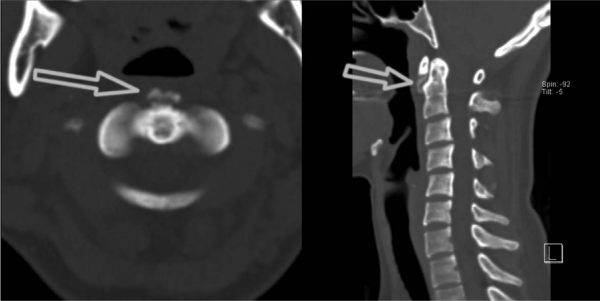

・脊髄硬膜外血腫

脊髄を覆うものとして内側から軟膜、くも膜、硬膜があるが硬膜外血腫とは何らかの原因により一番外側の硬膜と脊柱管の間に血腫ができる病態。

発症頻度は10万人に0.1人と稀な疾患であるがMRIの普及で近年増えているという。

抗凝固薬内服患者や出血傾向の患者で特に疑う。

軽微な外傷、咳やくしゃみ、重いものを持ったものなどを契機に突然発症。

(脊髄静脈には静脈弁がないので咳やくしゃみのように胸腔内圧が上昇する状況において破綻しやすいという説もある。)

好発部位は下部頚椎〜上部胸椎。

頸部を動かした時に痛みが増悪

血腫ができた部位に一致した圧痛

疼痛から数時間後、脊髄圧迫により膀胱直腸障害や運動感覚障害が出現する。

(血腫は静脈性に作られるので徐々に血腫が増大して神経症状の出現に時間がかかる)

四肢麻痺や対麻痺が多いが片麻痺のこともありうる(脳梗塞と誤診されやすい)

【検査】

CT,MRI

CTでは以下のように脊髄内、脊柱管内に高吸収域として認められるが、鑑別として上がらないと見つけるのは容易ではない。

画像参照:https://www.yodosha.co.jp/rnote/gazou_qa/9784758115445_1a.html